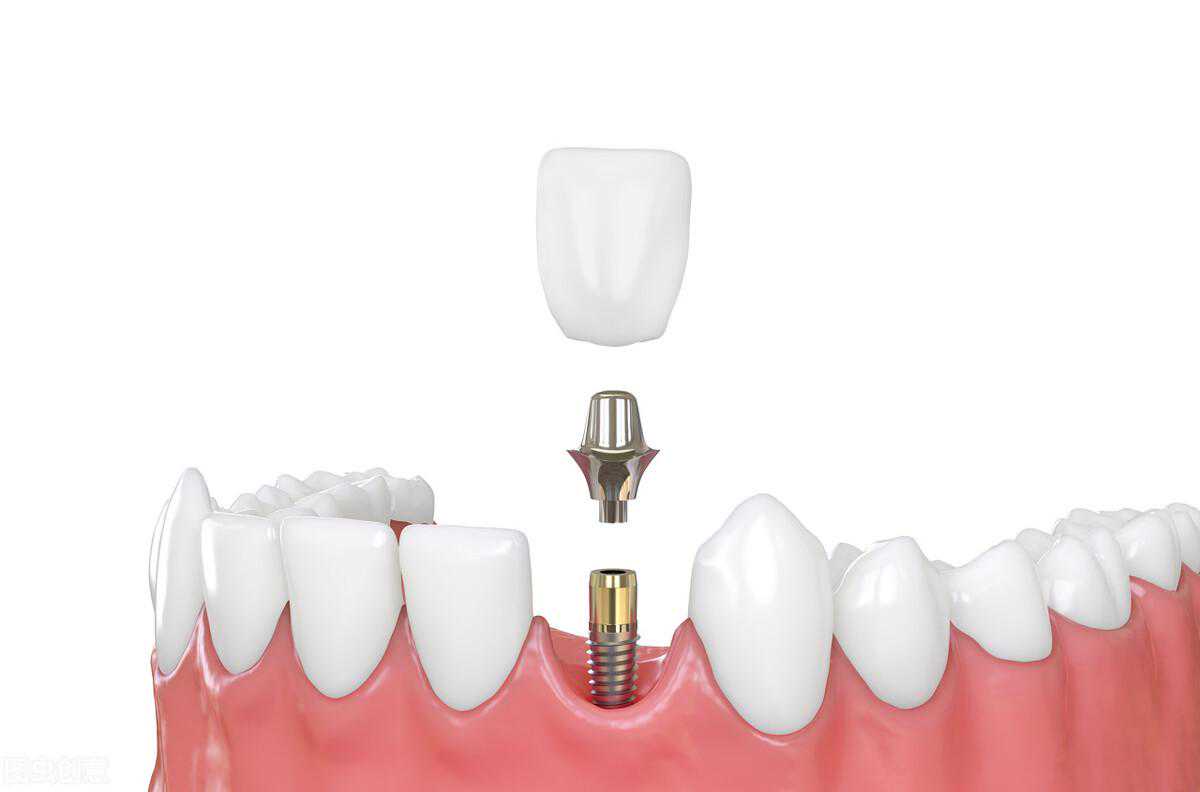

了解正常牙齿的结构之后,我们再一起看看下图:

这是种植牙的结构。露在牙龈外面的,是人造牙冠,也就是俗称的假牙、牙套。而深埋在牙龈和牙槽骨里面的部分,叫种植体,可以理解成人造牙根,同样也是为了固定和支撑牙齿。

但是,人造牙冠和种植体之间没办法直接连接在一起,他们之前需要一个桥梁,也就是基台,基台下部分是螺纹结构,可以和种植体牢牢结合在一起,上部分则是多面体形状,可以固定人造牙冠。

人造牙冠、基台和种植体,这三者合在一起,就形成了种植牙。